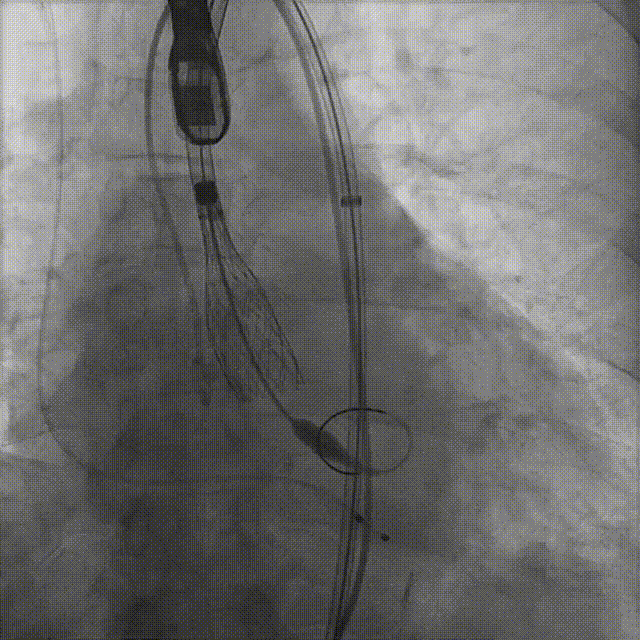

病例概览

患者病史 体检发现心脏瓣膜病半月余,平素无症状 ,有高血压病史。 后来院复查诊断为:主动脉瓣狭窄(重度)、先天性主动脉瓣二叶瓣畸形、心室肥厚、升主动脉扩张心功能 I 级(NYHA 分级)、高血压病 2 级(极高危)。 术前 CT:Type0型二叶瓣,瓣叶增厚,无钙化,类风湿性;瓣环径25.6mm,LVOT稍收窄,瓣环水平夹角66.6°,轻微横位心;左右冠开口高度可,瓣叶不长,无冠脉风险;心室收缩末内径约32mm,室壁增厚;外周入路无明显迂曲,无钙化、双侧内径可、双股中分叉,右侧为主入路能够支持20F大鞘通过。 造影角度及入路:LAO 6° CAU 13° 手术策略 采用右侧股动脉为主入路,左侧为辅助入路,常规穿刺。推荐使用20球囊预扩,预装TAV29瓣膜,初始定位对齐瓣环上0mm开始释放。 手术过程 20号球囊预扩无明显腰征 输送器过弓跨瓣顺滑 80%工作位观察 术后造影,瓣膜释放位置良好,无瓣周漏 术后超声:人工生物瓣释放后形态满意,瓣叶开放、关闭活动良好,无瓣周漏;跨瓣血流速度降至 2.5m/s,平均压力梯度6mmHg,符合手术预期。 Prostyle A®预装干瓣——“刚柔并济”助力临床最优化解决方案: 丝滑过弓能力:Prostyle A®短瓣架设计联合远端超滑亲水涂层,即使没有联合使用snare,都可以柔顺过弓,该例横位心的患者更好的展现了输送系统的柔顺性; 平衡的径向支撑力:该例患者Type0型二叶瓣,术后形态展开良好且无瓣周漏,在横位心等复杂情况下实现稳定锚定。 80%可回收设计:80%工作位观察,起搏时间更短,对患者损伤减少到最小,也利于术中精准调整瓣膜位置,保证术后效果。